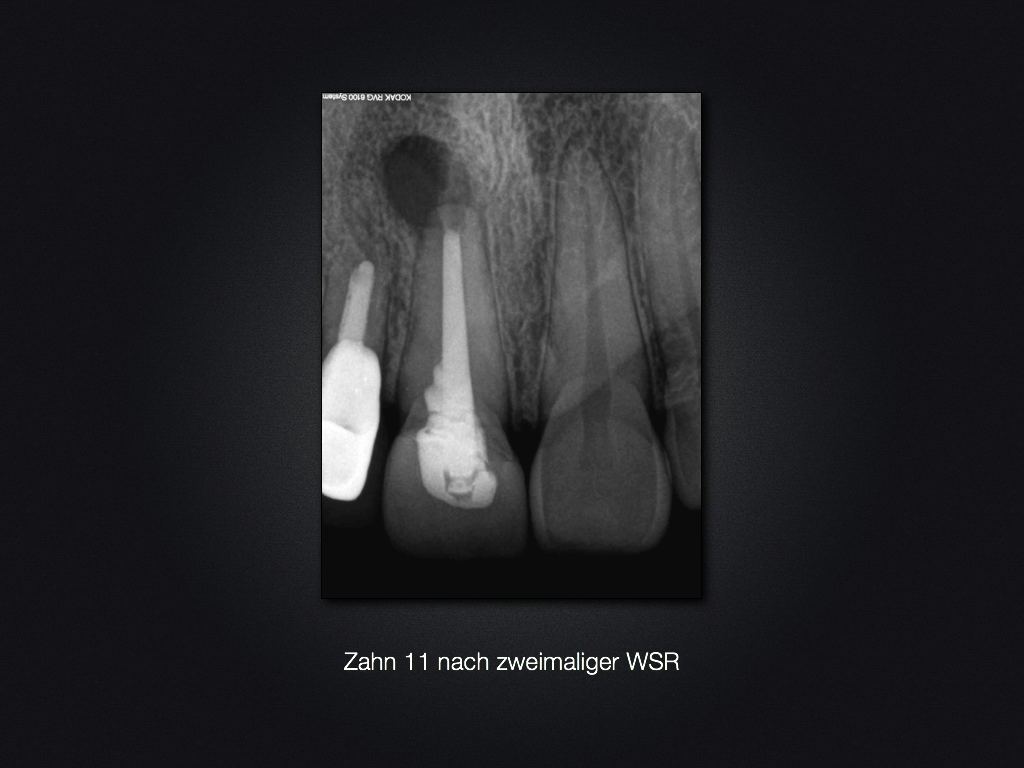

Und es heilt doch!